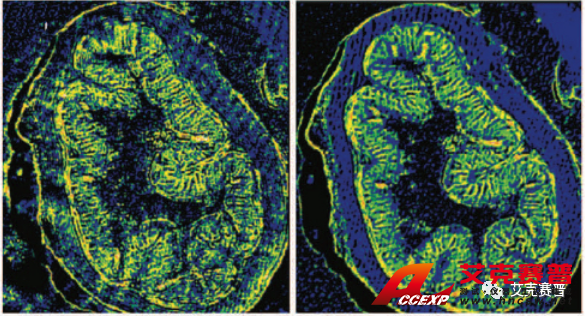

圖2顯示了布魯克已獲得專利的空間相干性抑制技術(shù)在采集激光紅外圖像時(shí)起到的改善作用。在左側(cè)的圖a和圖c中,可以看到激光束的干涉條紋對成像結(jié)果的影響。圖像看起來很模糊,有條紋和斑點(diǎn)。右側(cè)的圖b和圖d中相干性抑制技術(shù)在光源處消除了空間相干現(xiàn)象,從而采集到無比清晰的圖像(未經(jīng)任何后期處理)。

圖2:布魯克的空間相干性抑制專利技術(shù)改善了使用QCL成像技術(shù)采集的紅外成像的質(zhì)量: 我們得到了(d)原本的紅外成像圖,而不是(c)中干擾的傷偽影、條紋和斑點(diǎn)I2,該成像未經(jīng)任何后期處理。